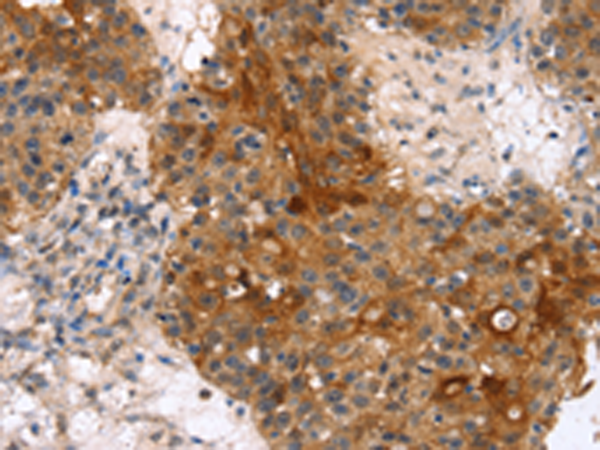

分类: 科研抗体货号: P10851别名: EVEC; UP50; ADCL2; ARMD3; DANCE; ARCL1A; FIBL-5; HNARMD应用: IHC反应种属: Human, Mouse, Rat